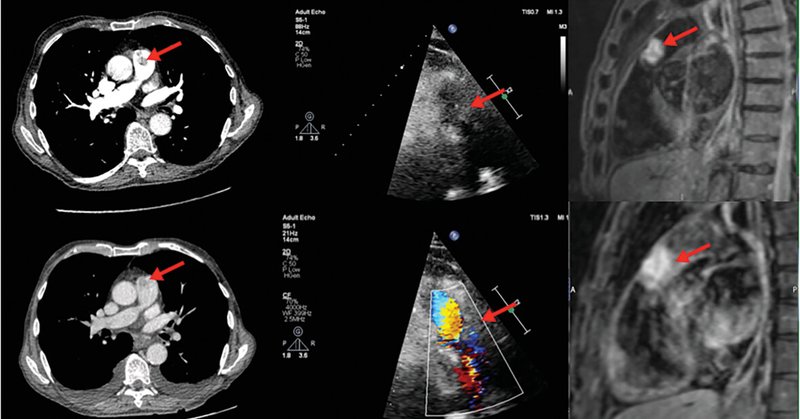

Case image article describing how multi-modality imaging led to a rare diagnosis: a main pulmonary artery fibroelastoma @NorthBristolNHS @amedany91 @omtoi #echofirst

A rare case of pulmonary artery fibroelastoma that demonstrates the importance of multimodality imaging and serial scans in reducing diagnostic uncertainty.

Pleasure to present a rare case of main pulmonary artery fibroelastoma at #EACVI2023 today. Excellent congress and fascinating cases throughout the session. @amedany91 @omtoi